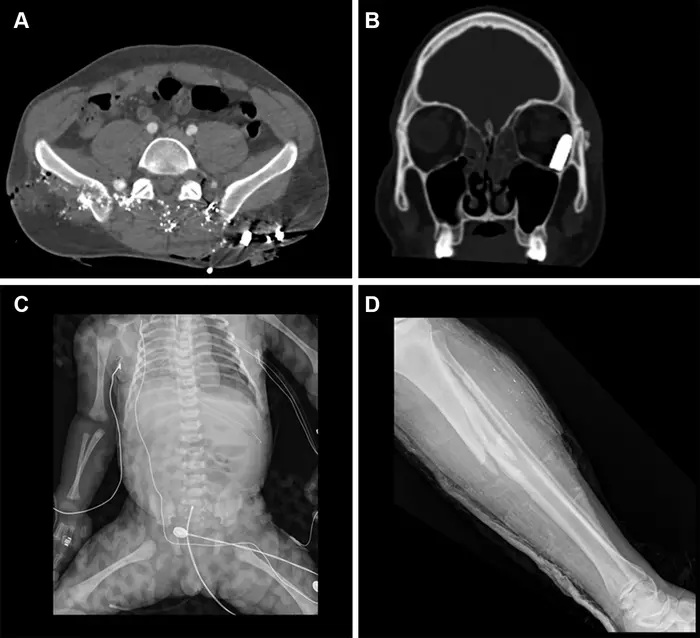

Representative injuries in patients from the mass casualty incident of October 7, 2023.

Representative injuries in patients from the mass casualty incident of October 7, 2023. (A) Axial CT scan at the pelvic level in a 34-year-old male patient shows multiple shrapnel fragments in the pelvis, resulting in fractures of the pelvic bones and lumbar vertebrae (not visible on this image). (B) Coronal reconstruction of a head CT scan in a 20-year-old male patient shows penetrating trauma to the left eyeball with a retained bullet in the orbital cavity. (C) Radiograph of a fetus delivered by emergency cesarean section from a critically injured mother shows a left pneumothorax and catheter in place. (D) Radiograph in a 25-year-old female patient shows a comminuted fracture in the tibial metaphysis with fragment displacement and multiple bony fragments in the surrounding soft tissues.